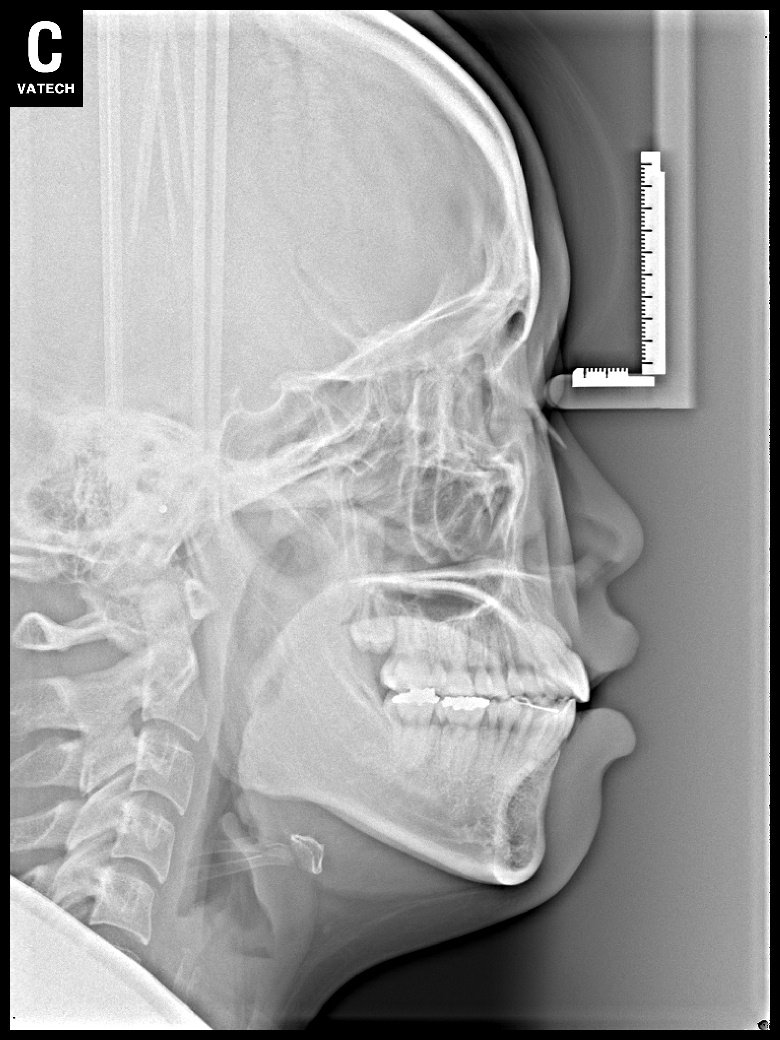

치료 전 사진입니다.